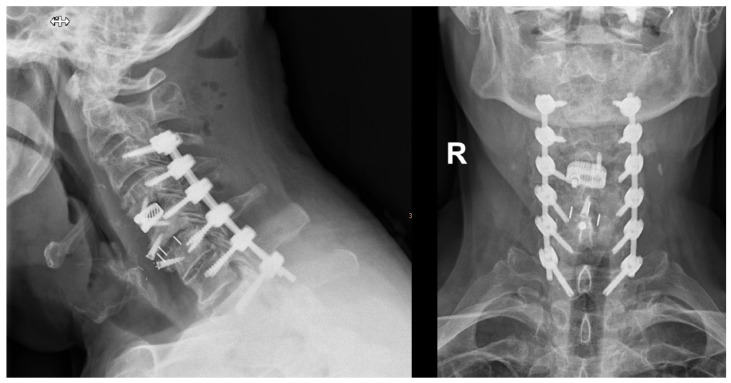

背景/目的:虽然具有生物力学优势,但颈椎椎弓根螺钉置入在技术上具有挑战性,因此通常只能在导航的帮助下在中心进行。本研究的目的是在一项大型单中心队列研究中,利用术中成像和使用导航高速钻头的工作流程分析导航颈椎椎弓根螺钉(CPS)置入的准确性和安全性。方法:我们对2018年1月至2024年6月期间接受后路颈椎或颈胸内固定术的205例患者进行了回顾性分析。使用Gertzbein-Robbins分类评估准确性,0级和1级被认为是满意的。分析手术流程、术中影像及并发症。结果:共评估椎弓根螺钉1112枚,其中颈椎螺钉888枚,上胸椎螺钉224枚。0级801例(72.0%),1级250例(22.5%),2级56例(5.0%),3级5例(0.4%)。93.1%的颈椎螺钉置入0级和1级满意,100%的上胸椎螺钉置入满意(0级92.0%,1级8.0%)。3级骨折发生在C2、C3、C5、C6和C7,各1例。无植入物相关神经血管损伤病例。结论:本研究显示螺钉精确度高,并发症发生率低。螺钉错位无翻修手术,但发生螺钉松动7例。然而,回顾性设计和对术中影像的依赖限制了结果的普遍性。

Background/Objectives: While biomechanically superior, cervical pedicle screw placement is technically challenging, and therefore typically performed only in centers with the aid of navigation. The purpose of this study was to analyze the accuracy and safety of navigated cervical pedicle screw (CPS) placement using intraoperative imaging with a workflow using a navigated high-speed drill in a large single-center cohort. Methods: We conducted a retrospective analysis of 205 patients undergoing posterior cervical or cervicothoracic instrumentation between January 2018 and June 2024. Accuracy was assessed using the Gertzbein-Robbins classification, with grades 0 and 1 considered satisfactory. Surgical workflow, intraoperative imaging, and complications were analyzed. Results: A total of 1112 pedicle screws, including 888 cervical and 224 upper thoracic screws, were evaluated. 801 were grade 0 (72.0%), 250 grade 1 (22.5%), 56 grade 2 (5.0%), and 5 grade 3 (0.4%). Cervical screws achieved satisfactory placement grades 0 and 1 in 93.1%, and upper thoracic screws in 100% (92.0% grade 0, 8.0% grade 1). Grade 3 breaches occurred in C2, C3, C5, C6, and C7, with one case each. There were no cases of implant-related neurovascular injuries. Conclusions: This study demonstrates high screw accuracy with a low observed complication rate. No revision surgeries were required due to screw malposition, but 7 cases of screw loosening occurred. However, the retrospective design and reliance on intraoperative imaging limit the generalizability of the findings.